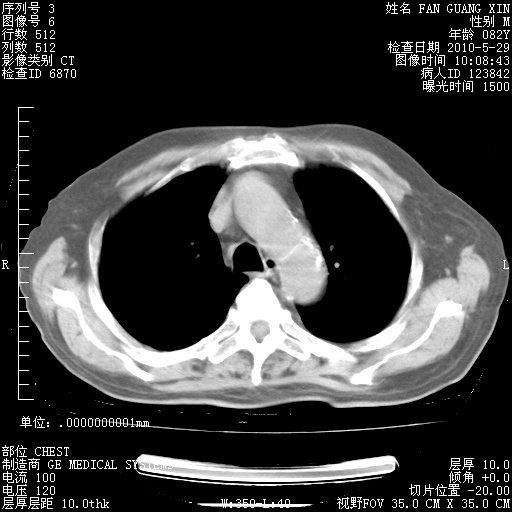

治疗3周后的肺部CT纵隔窗

从胸部影像学来看,的确有好转。至于目前为何发热不甚清楚?除了发热还有其他症状如有无喀痰,痰呈丝状吗?等等。尽量搜寻有无致发热其它可能原因?真菌?其它?如果的确无其他致发热的原因,考虑将甲强龙调至60-80mg bid/日。免疫全套基本无异常,考虑多系特发性肺间质纤维化

阅读此次胸部CT,肺间质渗出性改变较入院时有吸收。目前从体温、白细胞、中性分叶明显增高,肯定存在细菌感染(发生医院感染哦,若无消化道及泌尿系统等感染的依据,肺部感染可能大)。若你院头孢哌酮舒巴坦钠耐药率较高,同意你的方案,若48小时体温仍高,可考虑使用碳青霉稀类抗菌药物,同时可予超声雾化、注意滴数时加大液体量。白蛋白33.30g/L较低哦,需加强营养等支持治疗。